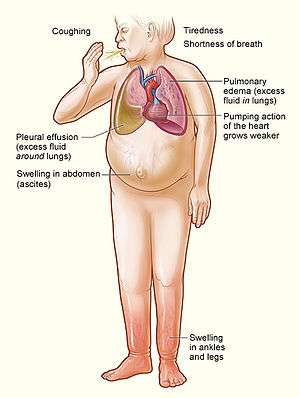

|

The major signs and symptoms of heart failure | |

| Symptoms | shortness of breath, feeling tired, leg swelling |

Heart failure (HF), often referred to as congestive heart failure (CHF), occurs when the heart is unable to pump sufficiently to maintain blood flow to meet the body's needs.[2][3][4] Signs and symptoms commonly include shortness of breath, excessive tiredness, and leg swelling.[5] The shortness of breath is usually worse with exercise, while lying down, and may wake the person at night.[5] A limited ability to exercise is also a common feature.[6] Chest pain, including angina, does not typically occur due to heart failure.[7]

Terminology

Heart failure is a physiological state in which cardiac output is insufficient to meet the needs of the body and lungs. The term "congestive heart failure" is often used, as one of the common symptoms is congestion, that is, build-up of too much fluid in tissues and veins.[18] Specifically, congestion takes the form of water retention and swelling (edema), both as peripheral edema (causing swollen limbs and feet) and as pulmonary edema (causing breathing difficulty), as well as ascites (swollen abdomen). This is a common problem in old age as a result of cardiovascular disease, but it can happen at any age, even in fetuses.

Heart failure symptoms are traditionally and somewhat arbitrarily divided into "left" and "right" sided, recognizing that the left and right ventricles of the heart supply different portions of the circulation. However, heart failure is not exclusively backward failure (in the part of the circulation which drains to the ventricle).

Left-sided failure

The left side of the heart is responsible for receiving oxygen-rich blood from the lungs and pumping it forward to the systemic circulation (the rest of the body except for the pulmonary circulation). Failure of the left side of the heart causes blood to back up (be congested) into the lungs, causing respiratory symptoms as well as fatigue due to insufficient supply of oxygenated blood. Common respiratory signs are increased rate of breathing and increased work of breathing (non-specific signs of respiratory distress). Rales or crackles, heard initially in the lung bases, and when severe, throughout the lung fields suggest the development of pulmonary edema (fluid in the alveoli). Cyanosis which suggests severe low blood oxygen, is a late sign of extremely severe pulmonary edema.

Backward failure of the left ventricle causes congestion of the lungs' blood vessels, and so the symptoms are predominantly respiratory in nature. Backward failure can be subdivided into the failure of the left atrium, the left ventricle or both within the left circuit. The patient will have dyspnea (shortness of breath) on exertion and in severe cases, dyspnea at rest. Increasing breathlessness on lying flat, called orthopnea, occurs. It is often measured in the number of pillows required to lie comfortably, and in orthopnea, the patient may resort to sleeping while sitting up. Another symptom of heart failure is paroxysmal nocturnal dyspnea: a sudden nighttime attack of severe breathlessness, usually several hours after going to sleep. Easy fatigability and exercise intolerance are also common complaints related to respiratory compromise.

Right-sided failure

Physical examination may reveal pitting peripheral edema, ascites, and liver enlargement. Jugular venous pressure is frequently assessed as a marker of fluid status, which can be accentuated by eliciting hepatojugular reflux. If the right ventricular pressure is increased, a parasternal heave may be present, signifying the compensatory increase in contraction strength.

Backward failure of the right ventricle leads to congestion of systemic capillaries. This generates excess fluid accumulation in the body. This causes swelling under the skin (termed peripheral edema or anasarca) and usually affects the dependent parts of the body first (causing foot and ankle swelling in people who are standing up, and sacral edema in people who are predominantly lying down). Nocturia (frequent nighttime urination) may occur when fluid from the legs is returned to the bloodstream while lying down at night. In progressively severe cases, ascites (fluid accumulation in the abdominal cavity causing swelling) and liver enlargement may develop. Significant liver congestion may result in impaired liver function (congestive hepatopathy), and jaundice and even coagulopathy (problems of decreased or increased blood clotting) may occur.

Biventricular failure

Dullness of the lung fields to finger percussion and reduced breath sounds at the bases of the lung may suggest the development of a pleural effusion (fluid collection between the lung and the chest wall). Though it can occur in isolated left- or right-sided heart failure, it is more common in biventricular failure because pleural veins drain into both the systemic and pulmonary venous systems. When unilateral, effusions are often right sided.